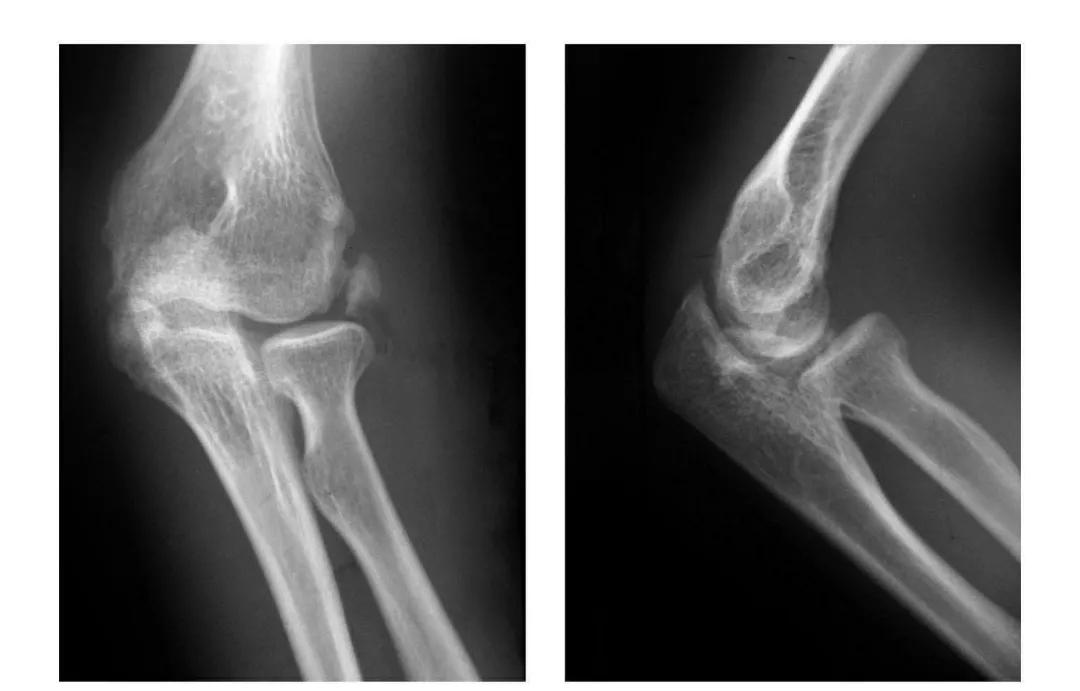

(二)部分骨折

本病亦称科-洛(Kocher-Lorenz)型骨折

例1:肱骨小头软骨面及其下方少量骨质呈“新月样”被剥脱,且向肘前上方移位并桡骨头前半部骨折。

例2:肱骨小头软骨面剥脱性骨折,致该小头新月状骨片被向前脱位的桡骨头顶向肘关节前上方,并尺骨干中段骨折(孟氏伸展型骨折)。